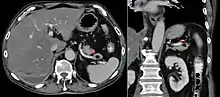

Гідроцефалія

.jpg.webp)

.png.webp)

Гідроцефалія — захворювання, що характеризується надлишковим накопиченням цереброспінальної рідини у шлуночковій системі головного мозку в результаті ускладнення її переміщення від місця секреції (шлуночки головного мозку) до місця абсорбції до кровоносної системи (субарахноїдальних цистерн (субарахноїдального простору)) — окклюзійна гідроцефалія, або в результаті порушення абсорбції — арезорбти́вна гідроцефалія.